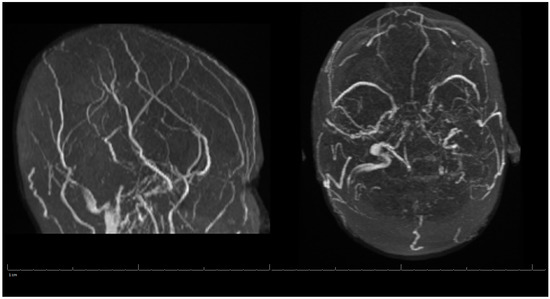

Additional labs showed Complete Blood Count (CBC) within acceptable limits, Basic Metabolic Panel (BMP) significant with glucose of 142 mg/dL, normal cardiac troponin level, and a negative urine drug screen. Urinalysis showed a small amount of blood but no evidence of infection. Genetic hypercoagulable labs, including antinuclear antibody, antineutrophil cytoplasmic antibodies, anti-cardiolipin, anti-Beta-2-glycoprotein, Factor V Leiden, and a lupus anticoagulant assay, were also unremarkable. Several hypercoagulable tests including antithrombin, protein C, and protein S were deferred, as results would have been confounded by the acute thrombotic event. Of note, the patient had abnormal findings on the lipid panel consisting of high cholesterol, triglyceride, and VLDL, and a low HDL level. Ultrasound Venous Doppler of the bilateral lower extremities showed no deep vein thrombosis. MRI brain/MRV (Magnetic Resonance Imaging (MRI) is a technique that uses magnetic fields and computer-generated radio waves to create images of organs and tissues in your body. Magnetic Resonance Venography (MRV) uses magnetic resonance technology and intravenous contrast dye to visualize the veins. Diffusion-Weighted Imaging (DWI) is a form of MRI that uses the diffusion of water molecules to generate images) with and without contrast confirmed acute venous infarct in the left subcortical frontal and parietal lobes as well as the left splenium of the corpus callosum. Thrombosis of the superior sagittal sinus, cortical veins, straight sinus, left internal cerebral vein, vein of Galen and the bilateral transverse sinuses, as well as the left sigmoid sinus, were also confirmed. A small hemorrhagic focus in the left occipital lobe was noted and was likely venous hemorrhages (Figure 1 and Figure 2). The final diagnosis was diffuse cerebral venous sinus thrombosis likely related to OCP use with possible contribution by recent COVID vaccination.

Figure 2. MRV of the Head during Hospital Admission.